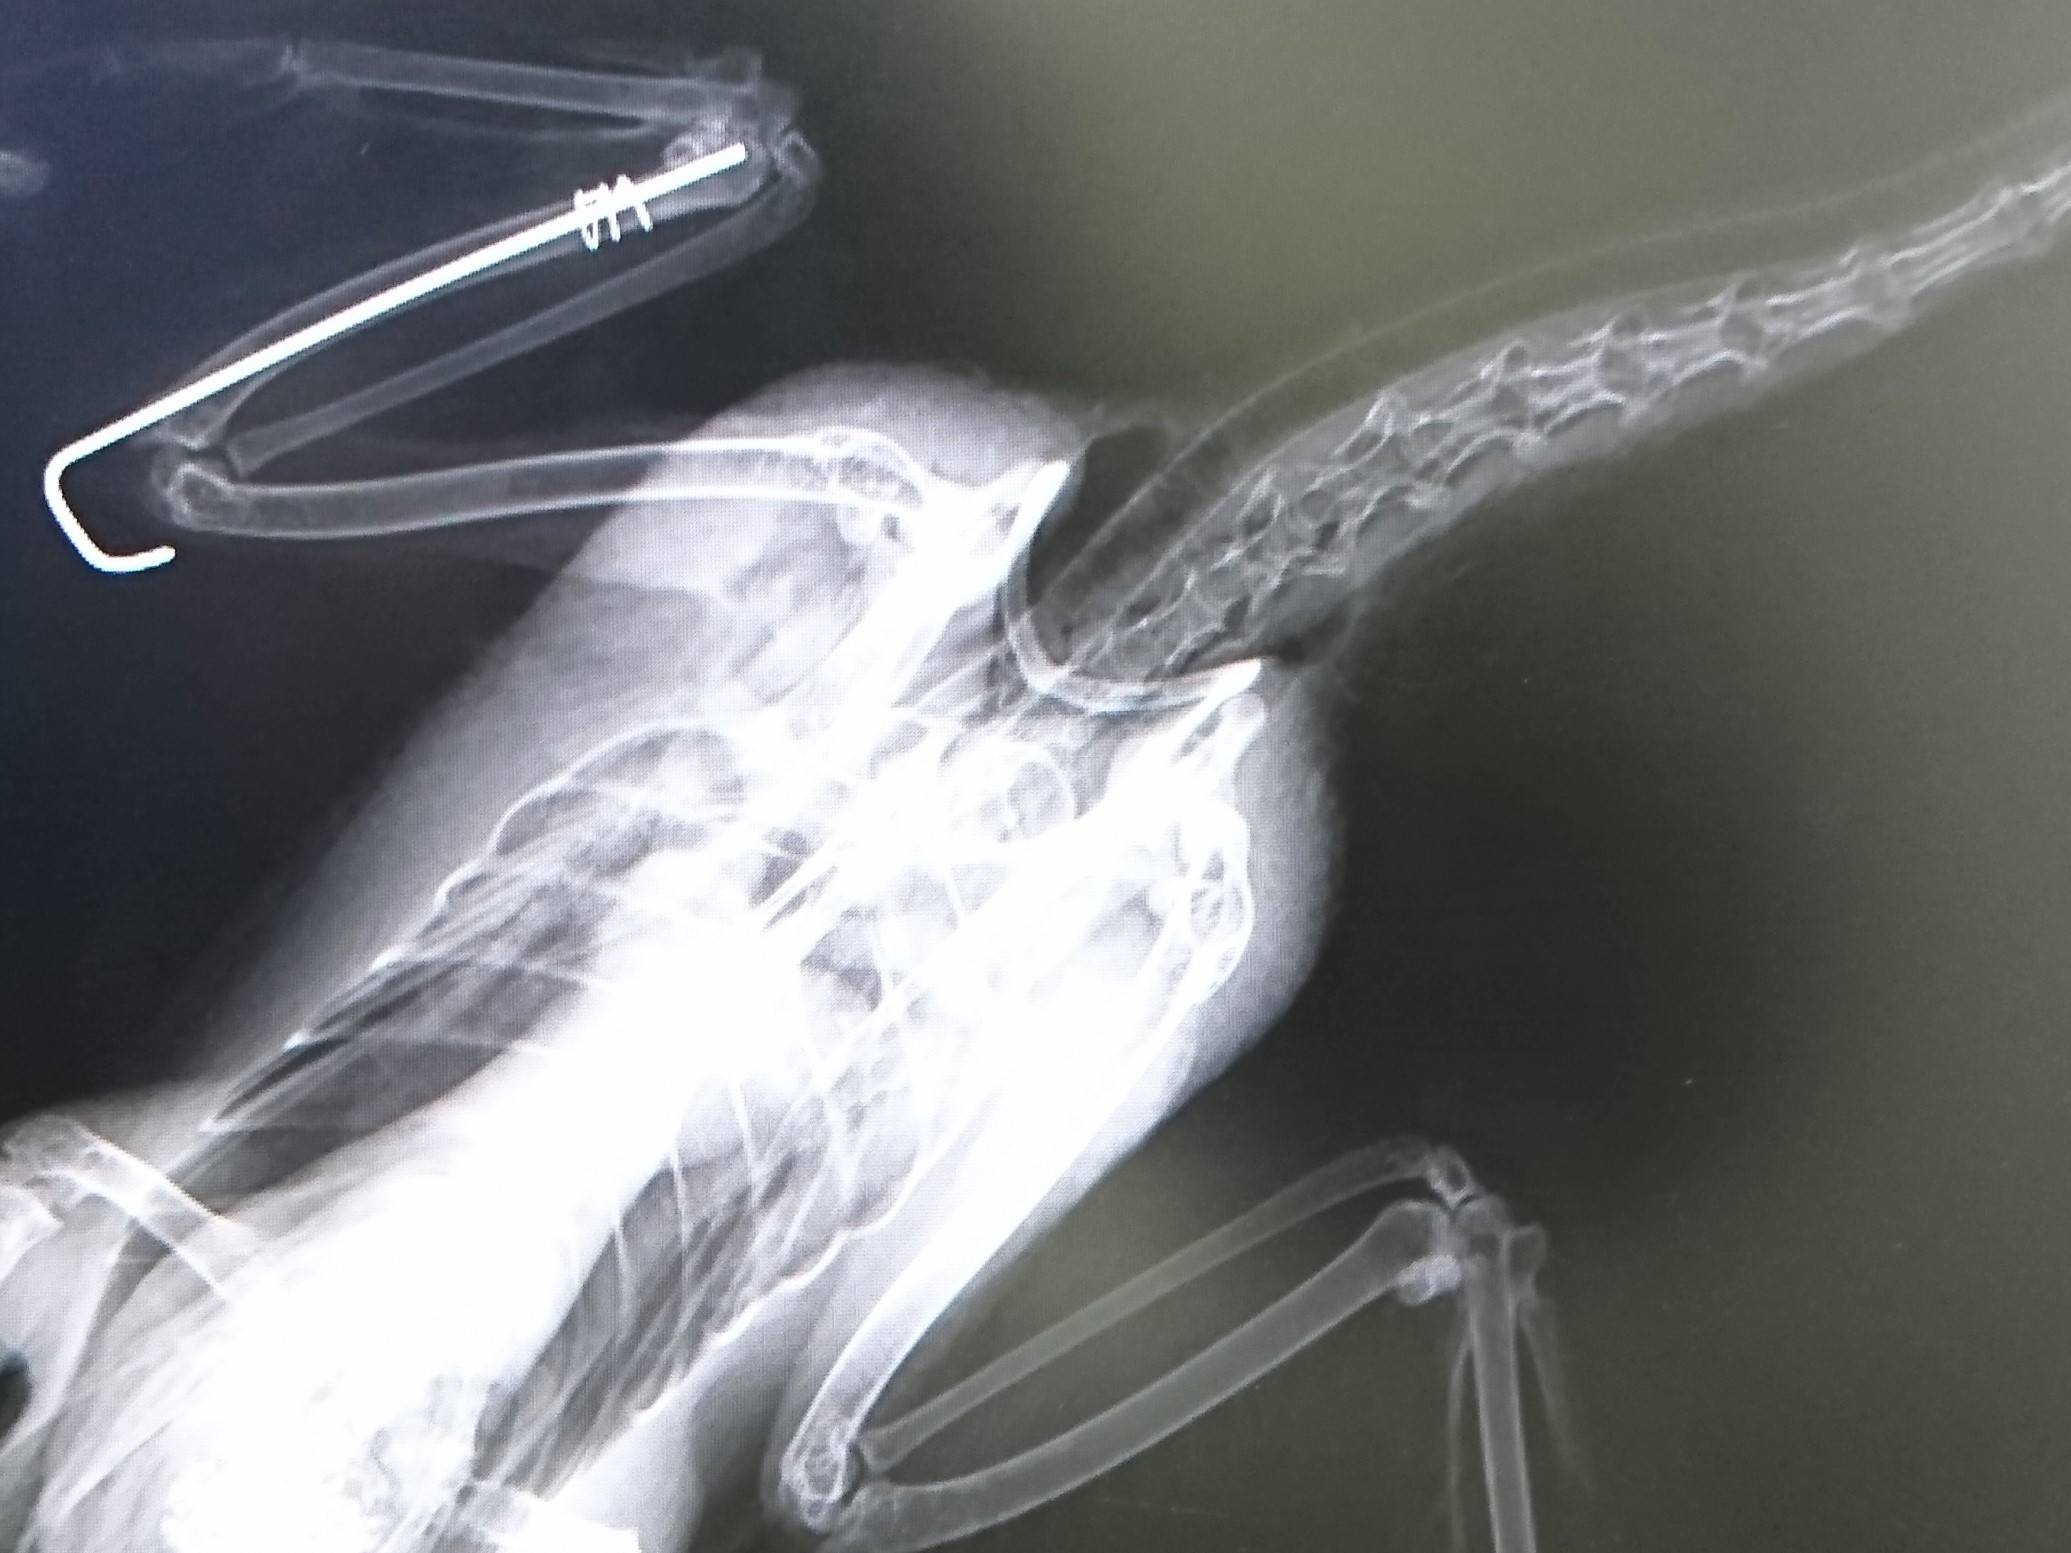

こちらは手術直後のレントゲン画像です。

これでしばらく安静。 ...手術して約2か月後